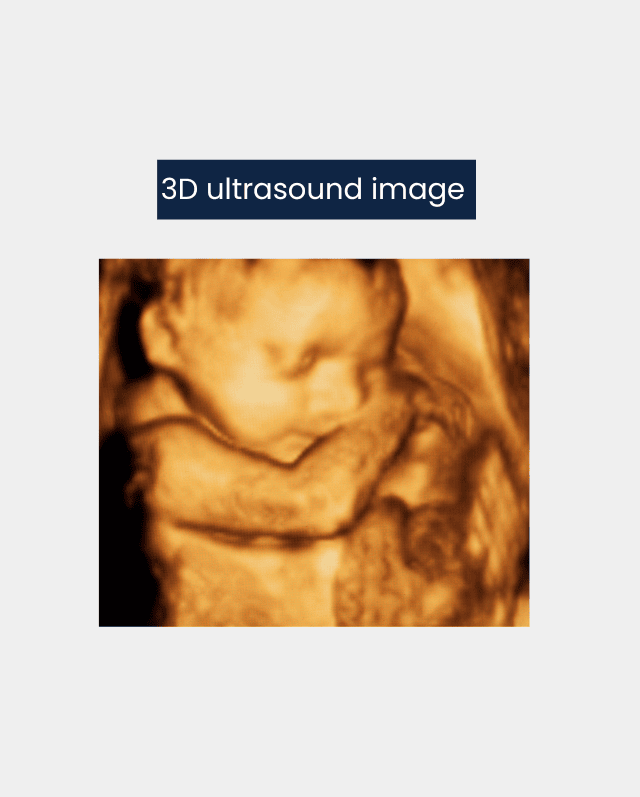

It is a more advanced technology in ultrasound imaging, which shows three-dimensional images of the fetus or the heart. 3D ultrasound machines show a more detailed picture than 2D ultrasound.

The pictures are orange, golden coloured and are created by reflected waves and angles which differ from one another.

Then these images integrate the information into high-speed computing software to create a 3D image.